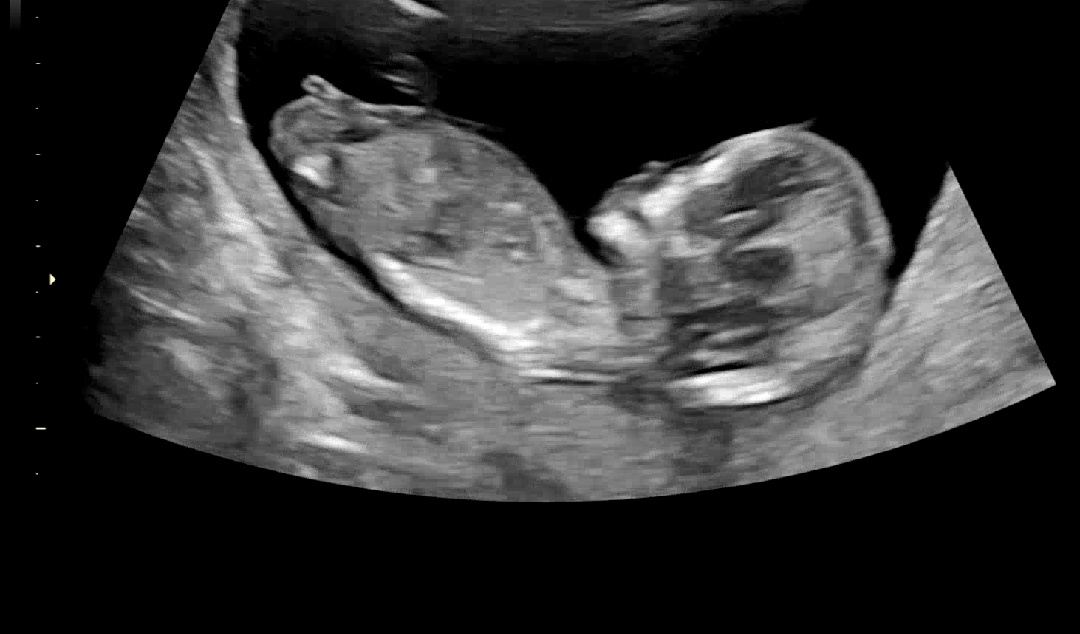

12주4일 뭐가 보이는데 크기를 볼 때 탯줄 같기도 하고.. 어떻게 보이시나요?

아들일까요 딸일까요?